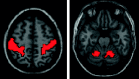

Thalamic motor functional connectivity averaged from 58 subjects. The red cross identifies the anatomic coordinates of the voxel used for deep brain stimulation. Images are in radiologic format. Section locations are MNI: z = −2, 0, 2, 4 (top left to bottom right).